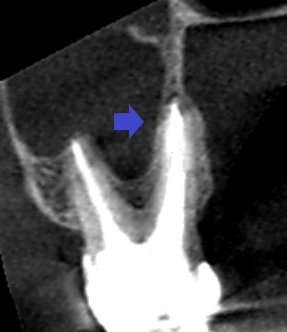

精密根管治療6ヶ月後の経過観察時の上顎第二大臼歯の矢状断のCT画像です。口蓋根の周りにみられた膿の影が消失し、歯槽骨が再生しています。

精密根管治療6ヶ月後の経過観察時の上顎第二大臼歯の冠状断のCT画像です。矢印の先に見えていた長い膿の影が消失しています。